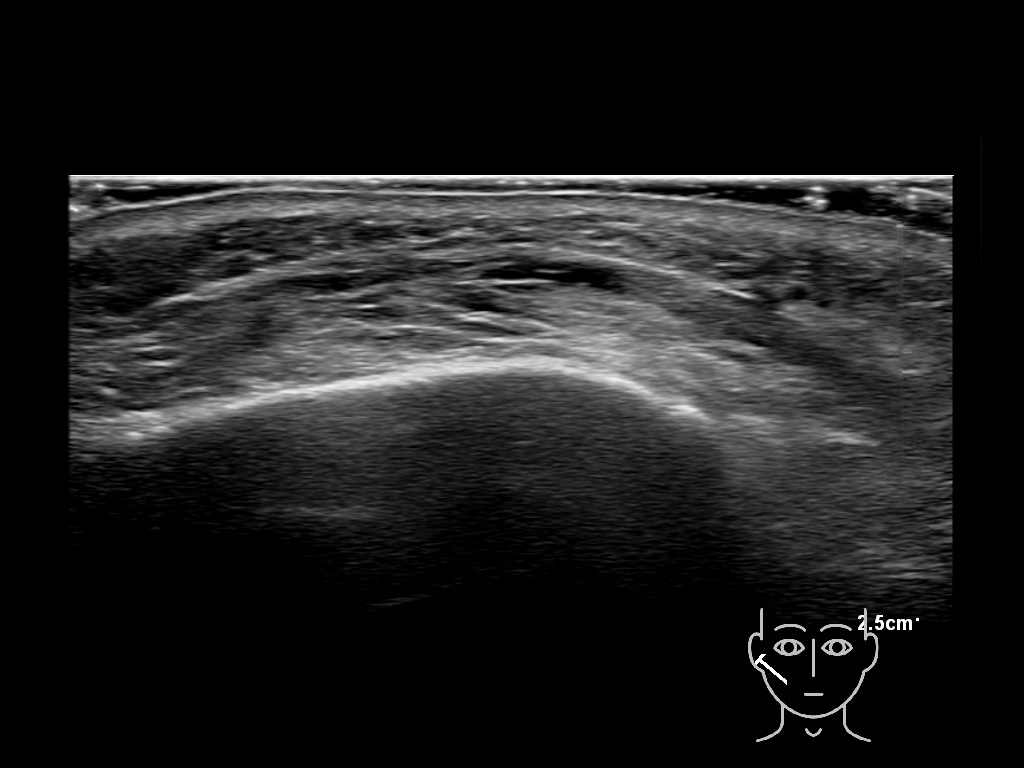

Filler deposits may end up unintentionally in the SMAS or fascial layers of the skin. Very often this will not lead to adverse events, however, adverse events ( nodules, migration / redistribution impaired muscle movement and smiling and malar edema) are are often related to filler ending up in the SMAS or fascia.

Study the first image to recognize the different layers. If you are sure about the layers, swipe to the second image to view the answer (if applicable).